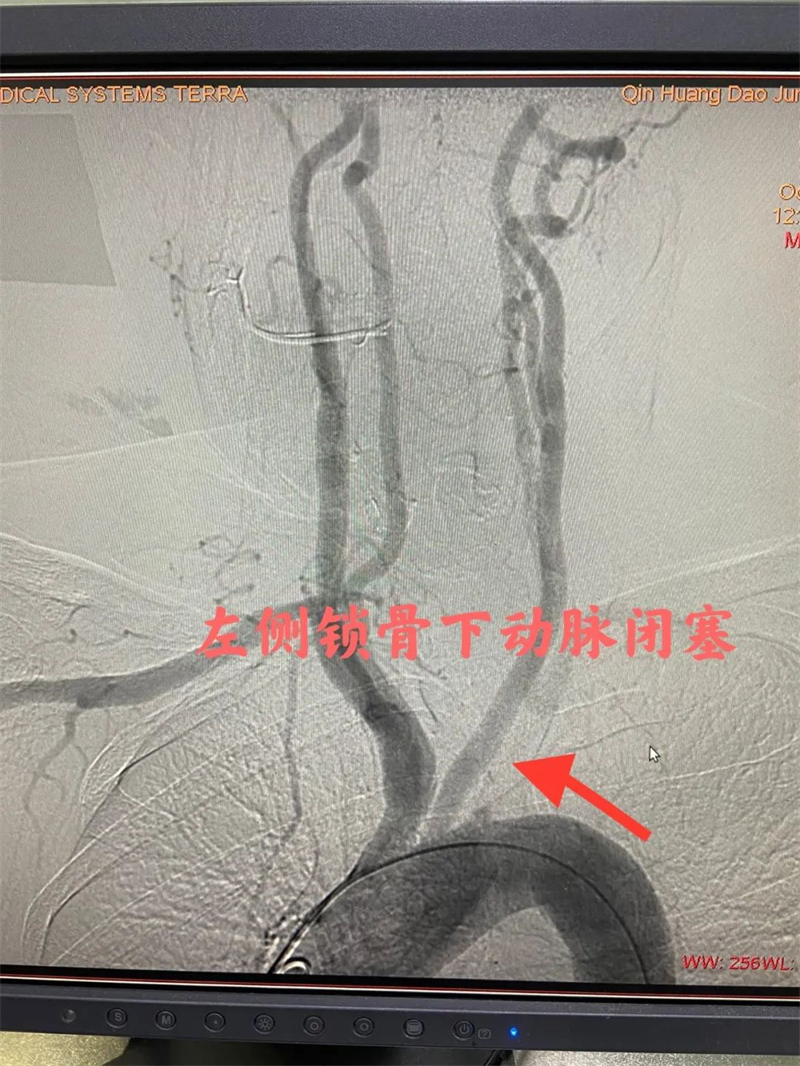

经过充分的准备后,心血管内二科及神经血管介入科团队通过股动脉穿刺,为患者顺利完成冠状动脉造影、肾动脉造影及左侧锁骨下动脉造影。冠状动脉造影结果提示患者前降支远段70%狭窄,确诊为冠状动脉粥样硬化性心脏病。肾动脉造影提示左侧肾动脉起始段中度狭窄,明确了肾动脉狭窄。左侧锁骨下动脉造影提示起始段次全闭塞。成功植入两枚支架,术后患者头晕缓解,左侧桡动脉搏动有力。